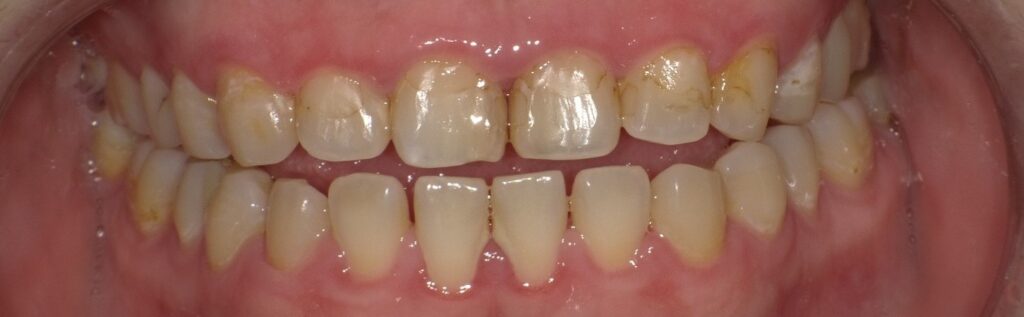

なまらホワイトニング1回目実施後の口腔内写真です。

全体的なくすみがとれてワントーン明るくなった印象です。

一方でもともと歯に白濁(ホワイトスポット)がある方は白濁が少し目立つように見えることがあります。また、レジン(歯科用プラスチック)で詰め物をしている部分は、ご自身の歯と比べると色の変化がほとんどないため、境目がわかりやすくなることもあります。

そして今回は実験的に、下の前歯に歯石を残した状態でホワイトニングを行いました。

ホワイトニング前ではあまり目立たなかった歯石も、歯が白くなることでかえって目立ってしまうことがお分かりいただけるかと思います。汚れや歯石が残ったままだと、薬剤の浸透や効果にも影響してしまいます。

そのため、実際の施術では必ずクリーニングを行ってからホワイトニングを実施しています。